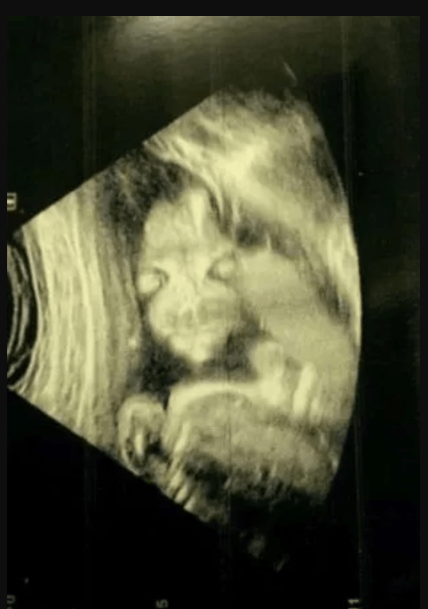

В Англії дівчина, на ім'я Джейд Бойленд поділилася своєю історією, як дала своїй дочці прізвисько "демонічна дитина". Річ у тому, що побачивши зображення свого майбутнього малюка на першому скринінгу, вона злякалася, оскільки жахлива постать була дуже схожа на зловісного персонажа з мультсеріалу "Зелені Обрубки" (Salad Fingers).

Про це пише Mirror. Джейд розповіла, що очікувала побачити класичний знімок бічного профілю дитини. Навіть сонографіст засміявся з дивного зображення, а потім швидко пояснив, що все виглядає нормально.

"Вона весь час дивилася назовні, ми не могли змусити її повернутися. Я намагалася змусити її рухатися. Не допомагало, вона не рухалася. Спочатку я злякалася, але потім мені стало смішно. Друзі та сім’я сміялися, коли побачили знімок. Я не думаю, що багато хто бачив щось подібне", — поділилася спогадами Бойленд.

Невдовзі після цього народилася Лідія Елвуд. Джейд ретельно її оглядала, але вже при народженні вона зовсім не була схожа на того мультяшного та моторошного персонажа.

Дівчина жартома охрестила Лідію Елвуд "дитиною-демоном" і стверджує, що особистість її "зухвалої" дочки відповідає цому прізвиську. Нині дівчинці вже сім років.